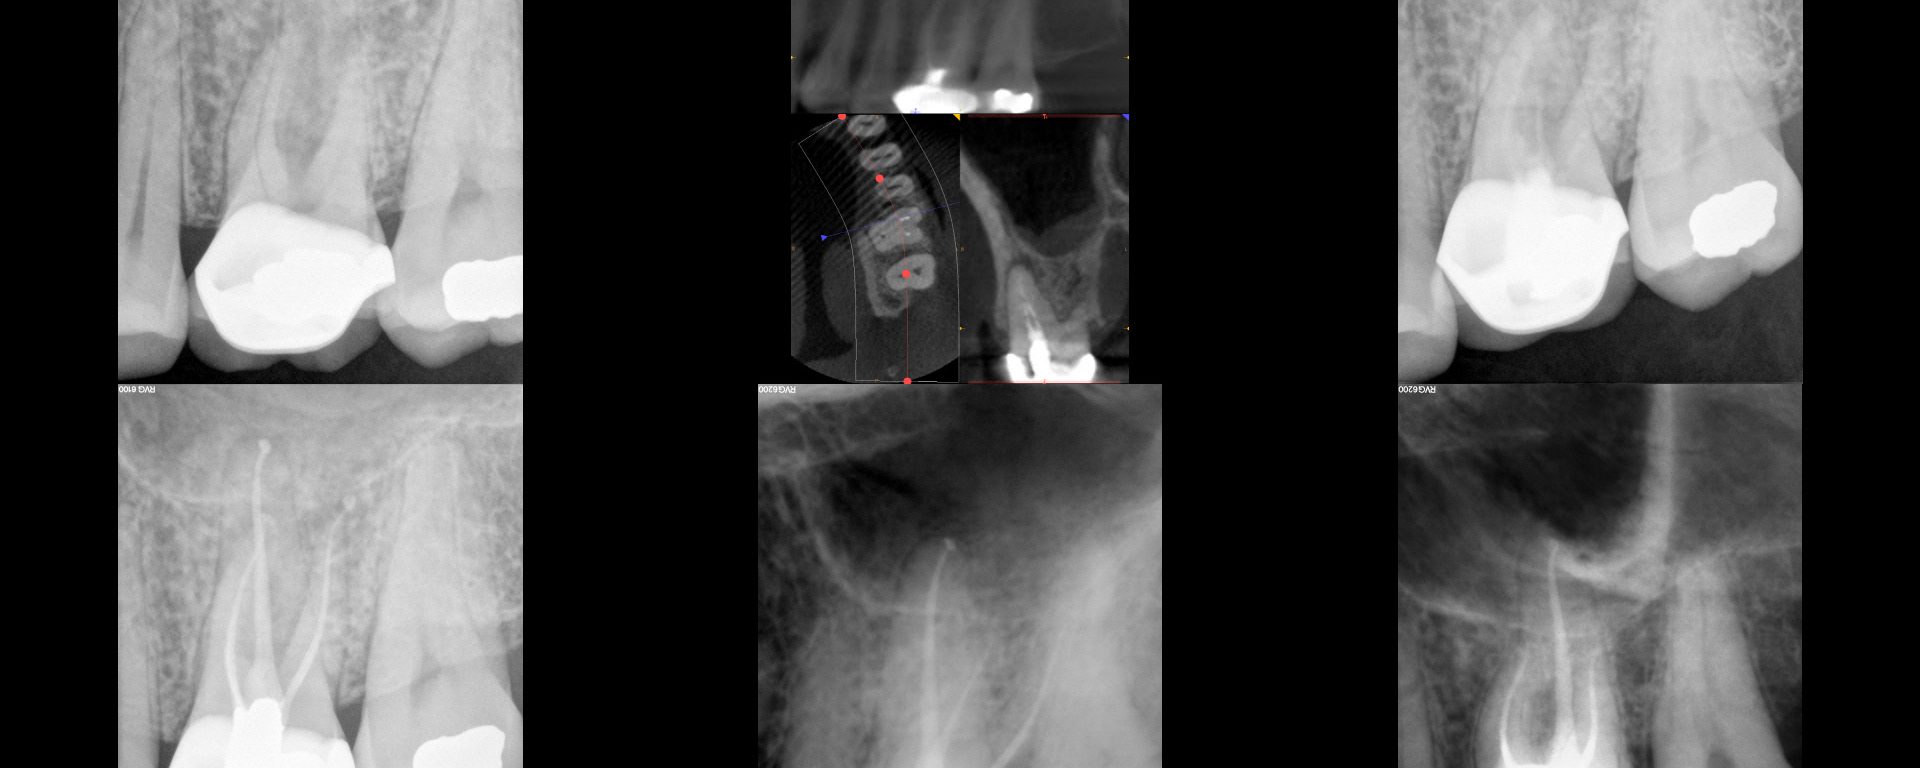

My lab tech. First saw him in 2001 with the separated instrument and finding around the mesial root on this endo that "does not meet the standard of practice in contemporary endodontics."  We thought was about 20 years old at the time.  Only findings were radiographic.  Panel 2 shows a two year followup in my […]

In today regarding this tooth I treated in 2005. Stepped access, two step crown repair with amalgam internal core with HF etched, silanated, opaqued and resin veneer. Shapes were ProFile S29 #5/.06 mesials, #6/.06 distals…large for that time but I was trying it out to see if it made any difference.  Normal shapes at that […]